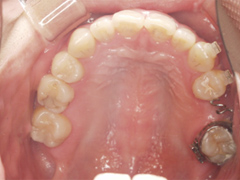

写真(1)口内写真

歯周病の進行により、上顎の歯は全て抜歯しなくてはならない状態

院長の吉本の診断は以下でした

・歯周病の進行により歯を支える骨が溶け、歯がグラグラになってきた

・もともとの咬み合わせの悪さ